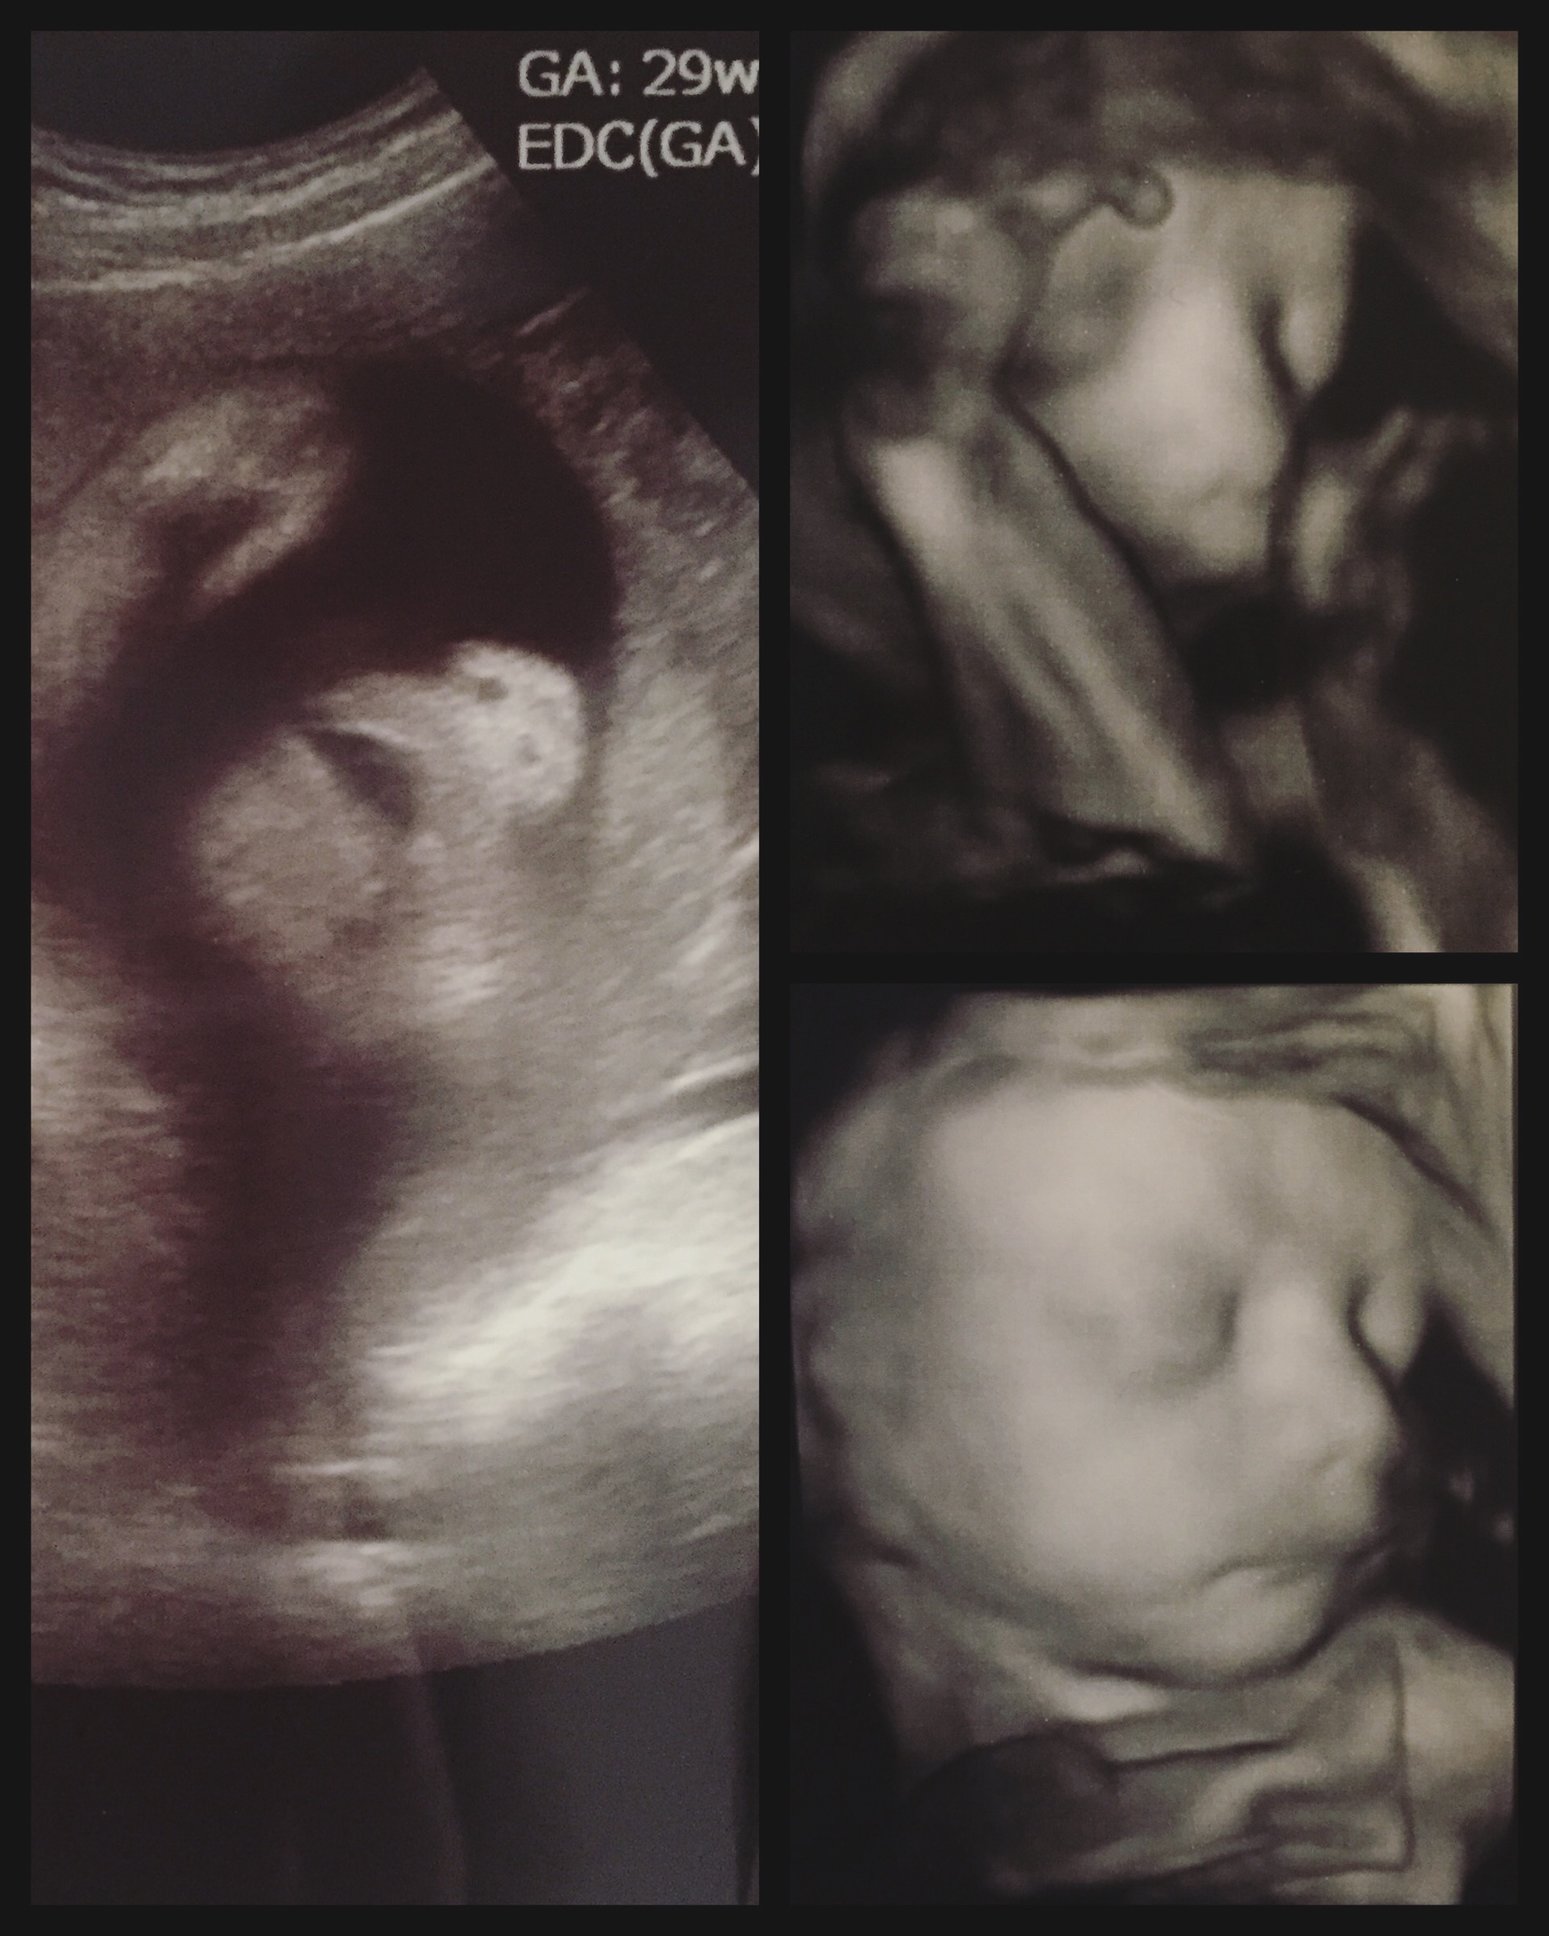

Our little babe at the anatomy scan this morning! LO refused to move their hands so we could get a 3d picture of the face haha Kinda looks like baby is praying!